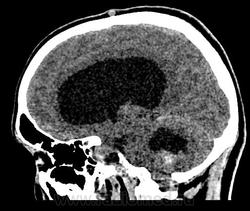

Девушка 30 лет. Поступила с диагнозом Эпилепсия. Неоднократные синкопы, начавшиеся после родов. Роды в начале марта, все благополучно. После родов, как-то так плохо все,шатает, голова болит. Через месяц обратилась в республиканскую больницу, выполнена кт- смешання гидроцефалия. Пролечили и выписали с диагнозом Дистония. Как-то так.

-признаки интравентрикулярной окклюзи выходных отверстий 4 желудочка, с резким расширением всех отдела желудочковой системы.

-резкое сужение охватвающей и большой цистерн

-выраженное расширение хиазмальной и предпонтийной цистерн

-межполушарная,латеральные щели и субарахноидальные пространства значительно уменьшены в объеме за счет увелиения желудочков и отека мозга

-истонены кости основания черепа,усилен рельеф внутренних костных пластин,углублено и расширено турецкое седло,опускание СЧЯ

-ствол и продолговатый мозг в дорсальном отделе уплощены,смещены вентрально

-в полости 4 желудочка объемное образование с учсатками кровоизлияния, с распространением каудально, признаки вклинения миндалин в БЗО,большая цистерна и САП кранио-вертебрального перехода не прослеживаются.

и добавлю,что это было за месяц до "нашей с ней встречи",тогда на кт в респусликанской б-це... кровушка лишь добавилась...